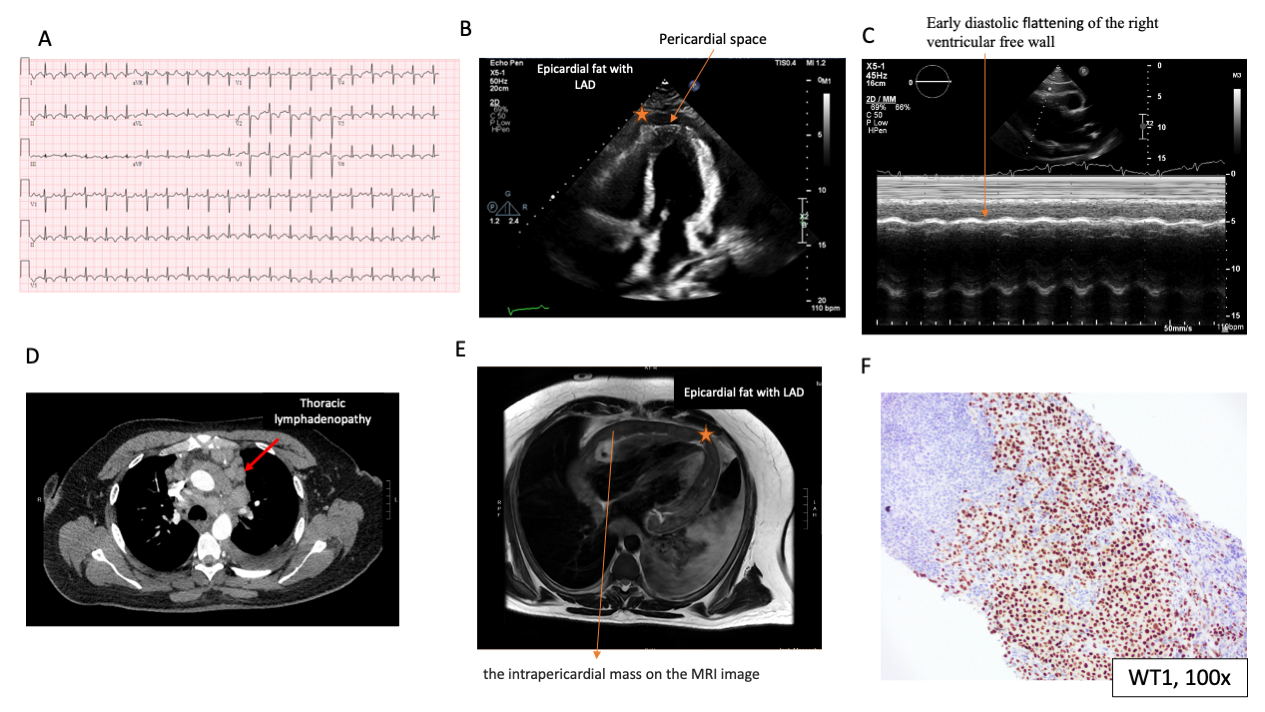

On presentation, his vital signs were notable for tachycardia to 113 and cardiac exam was notable for tachycardia, regular rhythm, no rubs or murmurs, nondisplaced precordial impulse, normal jugular venous pressure with Kussmaul sign, and pulsus paradoxus of 6. An electrocardiogram showed sinus tachycardia with diffuse ST segment changes (Figure A). His cardiac biomarkers were unremarkable (troponin 21). His labs revealed normocytic anemia with hemoglobin of 11 and erythrocyte sediment rate above assay. Echocardiogram demonstrated a circumferential complex pericardial effusion with echocardiographic evidence of early tamponade (Figure B, C). A pericardiocentesis was attempted with inability to advance wire within pericardial space. A malignancy workup was initiated. CT demonstrated multi-station thoracic and lower cervical lymphadenopathy, moderate left pleural effusion, and an intrapericardial mass with associated pericardial effusion (Figure D). Cardiac magnetic resonance imaging demonstrated a circumferential intrapericardial non-mobile mass measuring up to 22 mm in thickness posteriorly and the mass was isointense to myocardium indicating low-fat content (Figure E). A supraclavicular lymph node biopsy was obtained with immunohistochemical staining positive for WT1 and calretinin, consistent with metastatic epithelioid mesothelioma of pericardial versus pleural etiology (Figure F). A PET-CT subsequently showed a FDG-avid circumferential anterior pericardial mass and multiple pleural-based lesions concerning for metastatic mesothelioma. He was initiated on pemetrexed/carboplatin systemic chemotherapy. With systemic therapy, his disease has been stable for 6 months. Pericardial mesothelioma is a rare malignancy. This case underscores the diagnostic challenges associated with pericardial mesothelioma and the importance of cancer workup as part of the pericardial effusion workup.